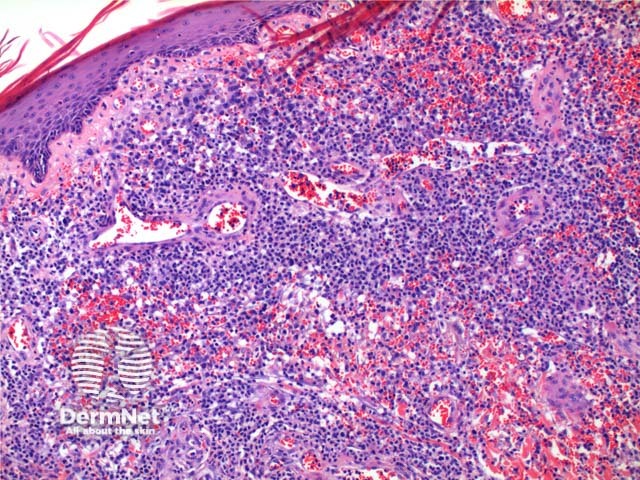

Scanning power of the pathology of lymphomatoid papulosis reveals a wedge-shaped inflammatory infiltrate extending to the deep dermis or superficial subcutaneous tissue (Figures 1 and 2). Note, it is made of prominent telangiectatic vessels and extravasation of erythrocytes in the case illustrated here (Figures 3 and 4). The lymphocytic population is comprised of a number of large CD30-positive lymphocytes (Figure 5). The mixture of cells forms a spectrum.

Figure 3

Figure 4